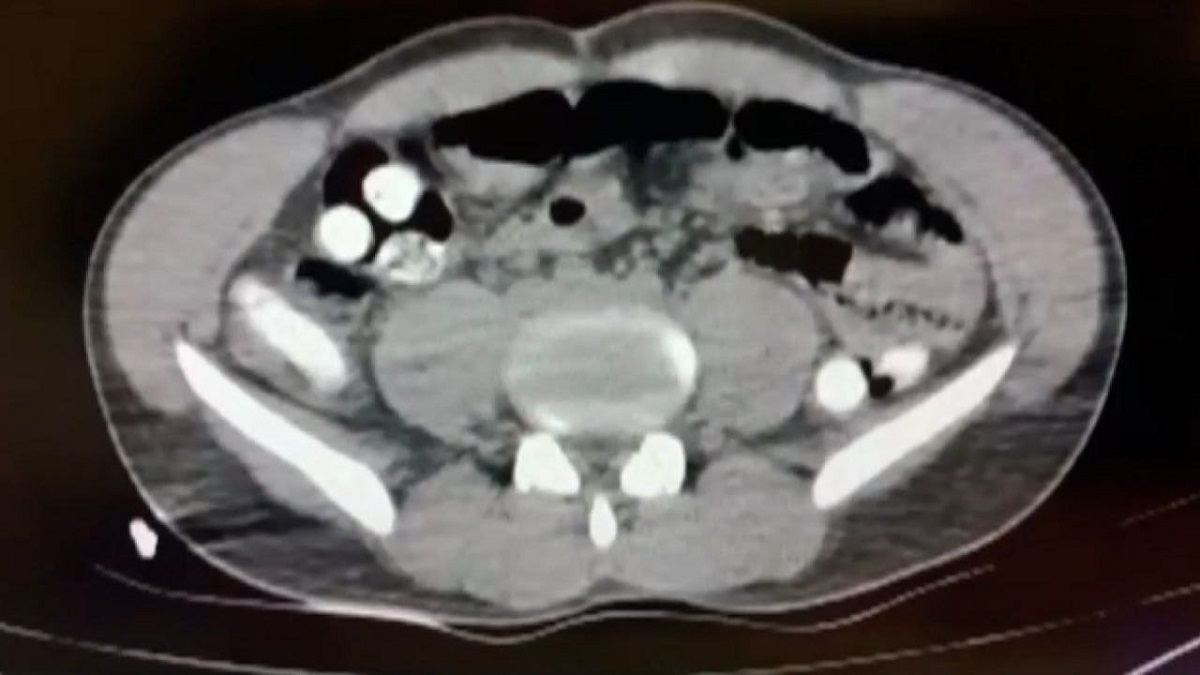

در عکس رادیوگرافی فرد مظنون مشخص شد که او با قورت دادن ۱۰۲ کپسول حاوی تریاک اقدام به حمل مواد مخدر کرده است.